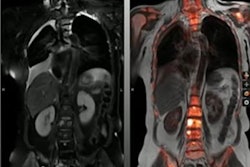

Dr. Adriano Dias highlighted results of a trial using Pylarify radiotracer in selecting patients for focal ablative therapy. Image courtesy of Adriano Dias.Forty out of 67 (60%) lesions identified in patients on PET, mpMRI, or PET/MRI were malignant, and 34 of these 40 (85%) were clinically significant, according to the findings. On a lesion-level analysis in these, the sensitivity of PET was higher than of mpMRI and PET/MRI (91% vs. 76% and 79%), but it showed a lower specificity (39% vs. 85% and 88%, p < 0.001). The calculated AUCs were 0.65 for PET, 0.81 mpMRI, and 0.84 for PET/MRI.